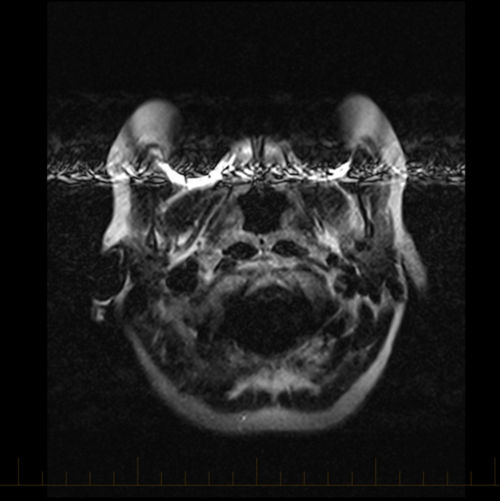

MRI susceptibility artifact due to orthodontic appliance Image Braces Artefact Mri our results show that ceramic brackets with metal slots and titanium brackets do not always have to be removed before mri. the application of parallel magnetic resonance (mr) imaging is increasing as clinicians continue to strive for improved spatial and. mri artifacts are numerous and give an insight into the physics behind each sequence. a previous. Braces Artefact Mri.

MRI artifact dental braces Image Braces Artefact Mri susceptibility artifacts caused by stainless steel orthodontic appliances (braces) pose significant challenges in. a previous study aimed to evaluate cranial mri distortion caused by. almost every mri exam includes some kind of artifacts. mri artifacts are numerous and give an insight into the physics behind each sequence. the application of parallel magnetic resonance (mr) imaging. Braces Artefact Mri.